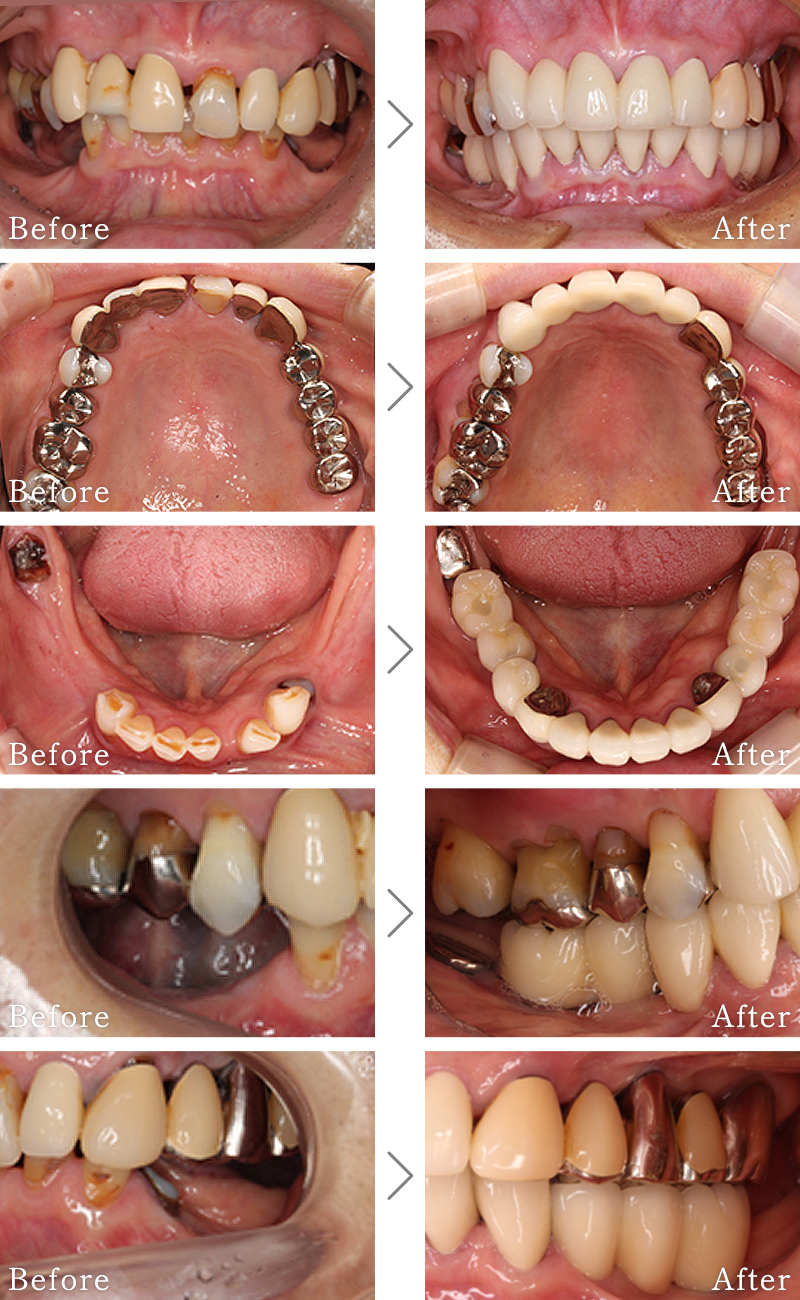

CASE1

主訴 入れ歯も合わず、しっかりと噛んで食事ができないとのことで来院されました。

治療法 上下ともにALL-ON-6と呼ばれる最少本数のインプラントで全ての歯を回復する治療を行なっています。歯の部分は全てセラミックで作成されています。

治療期間 5ヶ月

費用 CT:16,500円(税込)

+ 静脈内鎮静法:77,000円(税込)

+ ALL-ON-6×2:5,500,000円(税込)

合計:5,593,500円(税込)

副作用

• 歯周病に感染・発症し重度に進行するとインプラントが抜けてしまうことがあります。

• 手術後は数日間腫れが出る場合があります。